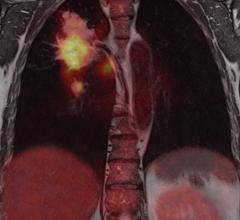

The variety of radiation therapy options continues to grow with the development of treatment planning software, imaging systems for guidance, linear accelerators and more. The external-beam radiation therapy (EBRT) market includes many different types of treatment, from traditional whole-body irradiation (WBI) to conformal radiation therapy (3-D CRT) and intensity-modulated radiation therapy (IMRT). Despite a major decline in 2009, the U.S. radiation therapy market is bouncing back, according to a study published in July by IMV Medical Information Division.[1] Improvements in technologies are helping to drive activity as clinics and hospitals implement advanced techniques to more accurately target and treat cancers.

In the past 20 years there have been considerable improvements in the treatment of prostate cancer. As it is across all radiation oncology, techniques have evolved from conventional external beam radiation therapy (EBRT), to more targeted therapies that are delivered in fewer visits. One of the latest notable trends in radiotherapy is the emergence of real-time image guidance for intensity-modulated radiation therapy (IMRT). For prostate cancer, radiotherapy is often deployed in conjunction with surgery (prostatectomy) or as curative therapy, depending on the stage of disease. As these new techniques emerge, it becomes more important for clinicians to identify which ones work most effectively and for which patients.